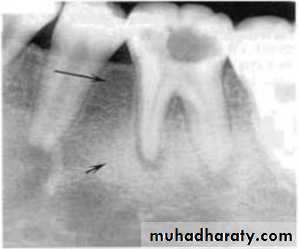

Cystic ameloblastoma displaced IDC (odontogenic origin)

Epicenter coronal to tooth

(odontogenic epithelium )

• A lesion (developmental salivary gland

• defect) below the IAC

• (non- odontogenic origin).